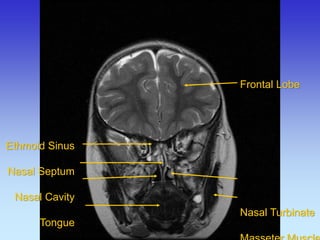

Ethmoid Sinus Nasal Septum Nasal Cavity Tongue

Frontal Lobe Nasal Turbinate Masseter Muscle